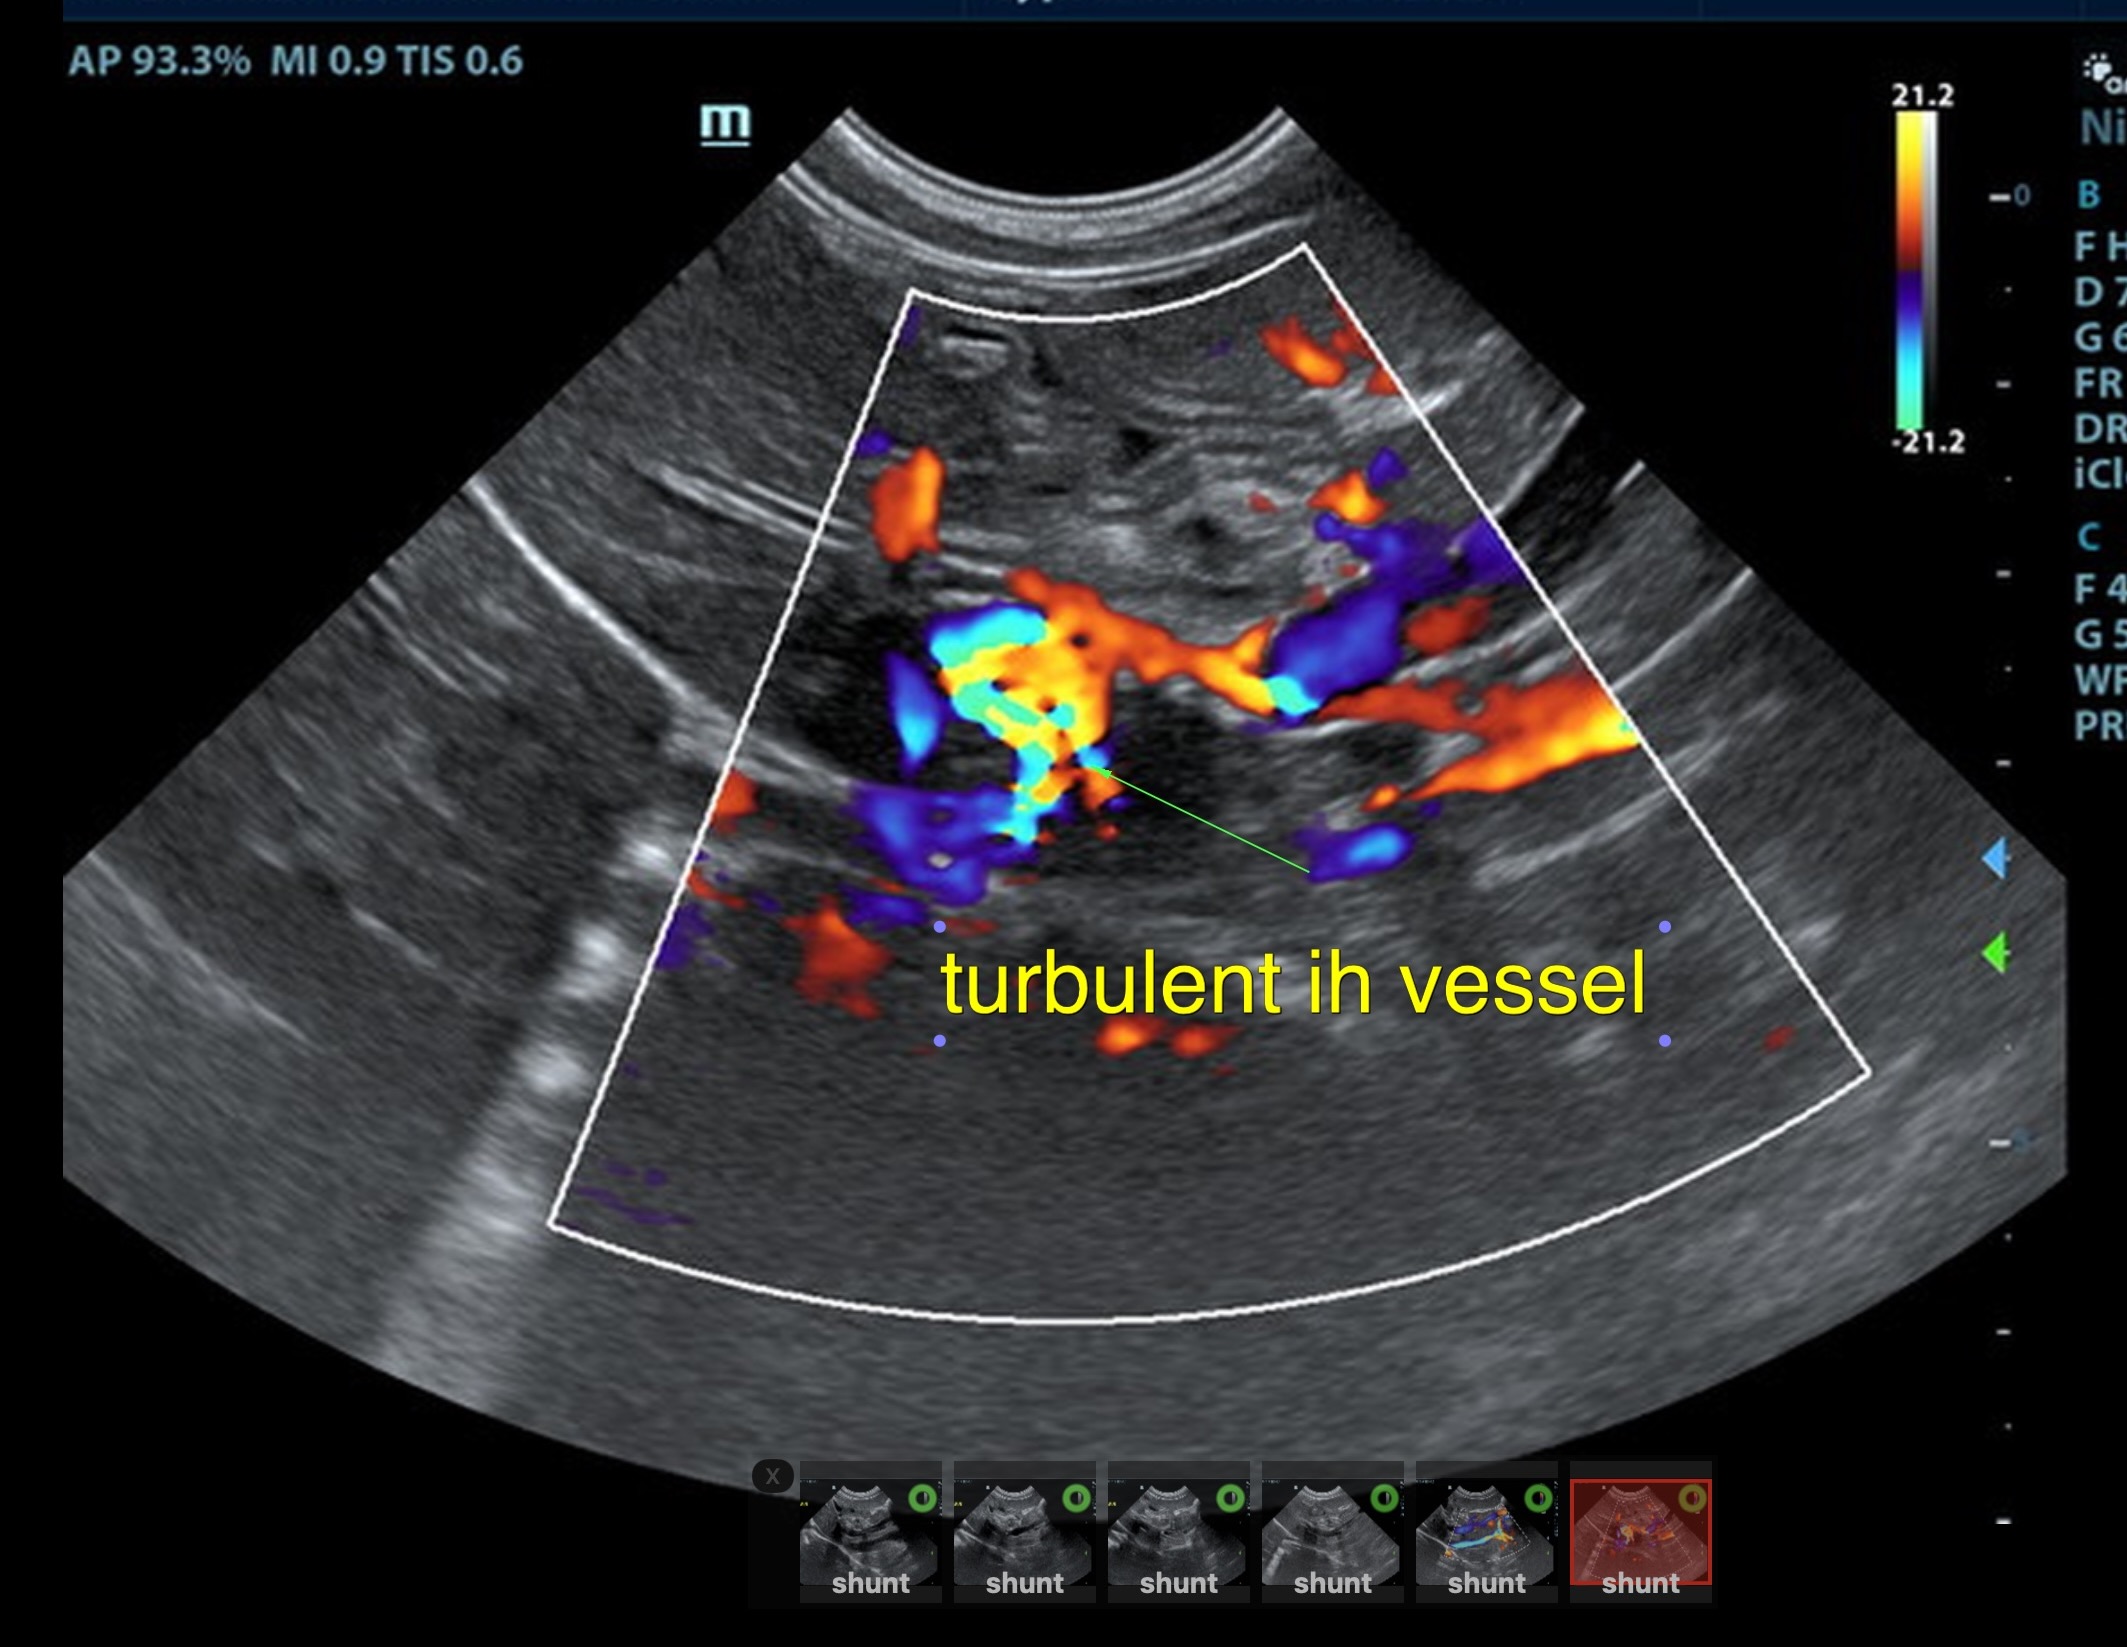

The liver was subnormal in size, yet the portal vein and vena cava ratio was 1:1. The portal veins were subnormal in size and measured 0.34 cm. The vena cava was enlarged and measured 0.34 cm. The vena cava was enlarged and measured 0.72 cm, aorta measured 0.4 cm. The branching of the portal vein appeared to be normal and of adequate volume. The portal vein and vena cava measured 0.5 cm each in the extrahepatic space. The splenic vein entry into the portal vein and gastroduodenal vein entry into the portal vein appear to be normal. There was one turbulent vessel in the region of the central branch of the portal vein, which may represent an intrahepatic shunt, but this could not be confirmed. The width of the shunt is approximately 0.76 cm. This is in position of central divisional shunt; however, right divisional origin cannot be completely ruled out. The gallbladder presented acceptably thin walls with primarily anechoic content. The cystic and common bile ducts were normal.